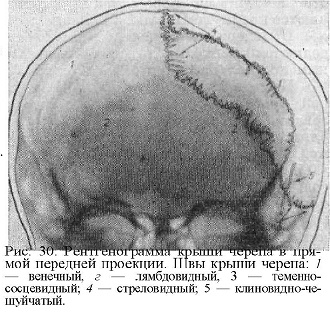

Анатомия детского черепа: Рентгеновские снимки и описание